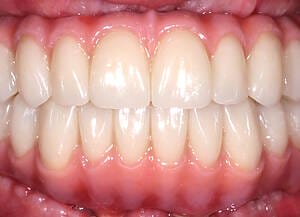

The moment Natalie saw her new smile, the emotion was undeniable. What had once been a source of discomfort, anxiety, and embarrassment had been completely transformed. Her new teeth restored full function and aesthetics, giving her back the ability to eat, speak, and smile without hesitation.

This result was more than cosmetic. It marked the end of a long journey filled with fear and hesitation, and the beginning of a new chapter defined by confidence and well-being. Natalie’s story is a powerful example of how modern dentistry, when led by skilled professionals and supported by cutting-edge technology, can restore much more than teeth.

My first look in the mirror with my new set of teeth was incredible. I’m in disbelief and I feel a bit overwhelmed because it looks so good. At the same time, it looks so natural, it is the shape of my natural teeth and smile. They feel comfortable, I can speak with them. I feel very confident that this will work very well for me.